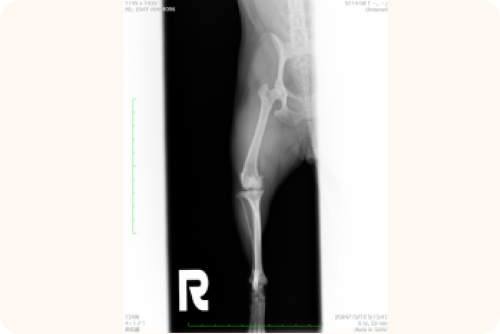

レントゲン検査

X線撮影により、以下の点を詳細に確認します。

• 膝蓋骨の位置と脱臼の方向

• 骨の変形や捻れ

• 変形性関節症の進行度

• 関節炎の有無

この検査結果は、手術の必要性や具体的な手術方法を決定する上で重要な情報となります。

骨の位置関係や、前十字靭帯損傷時に見られる特徴的な所見(ファットパットサインなど)を確認します。

視診や触診後、レントゲン検査を行い、骨がどのような位置にあるのかを詳しく調べます。また、レントゲン写真では膝の関節内にある脂肪組織の位置も確認します。この脂肪組織の位置が変わっていることで、前十字靱帯が傷んでいないかどうかの手がかりを得ることができます。